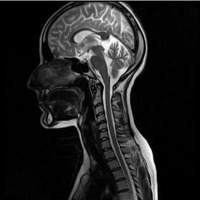

Umetno proizvedena magnetna polja nastanejo vedno, ko se elektrika uporablja v obliki enosmernega toka (DC), na primer v nekaterih železniških sistemih, pri proizvodnji aluminija in pri varjenju. MRI naprave v medicinske namene uporabljajo statično magnetno polje za izdelavo tridimenzionalnih posnetkov možganov in drugih delov telesa. Pri tej aplikaciji lahko izpostavljenost preseže običajno priporočeno mejno vrednost in sicer tako za osebje kot za pacienta.

Podatki za presojo tveganja zaradi izpostavljenosti statičnim magnetnim poljem so še vedno nepopolni, učinki tako imenovanih mešanih polj, ko prihaja do interakcije statičnih polj z drugimi elektromagnetnimi polji, pa so v veliki meri neraziskani. Številne nove tehnologije, na primer naprave za slikanje z magnetno resonanco (MR), uporabljajo kombinacijo različnih polj, kar pomeni, da jih je treba posebej temeljito raziskati.

V medicini se uporabljajo močna visokofrekvenčna EMS za segrevanje telesnega tkiva. Ta lahko lajšajo bolečine ali uničujejo rakave celice. Tovrstna polja uporabljajo tudi za produkcijo slik možganov ali drugih delov telesa s pomočjo magnetne resonance (MR). Izpostavljenost pacientov ali medicinskega osebja lahko preseže običajne varnostne mejne vrednosti za prebivalstvo.